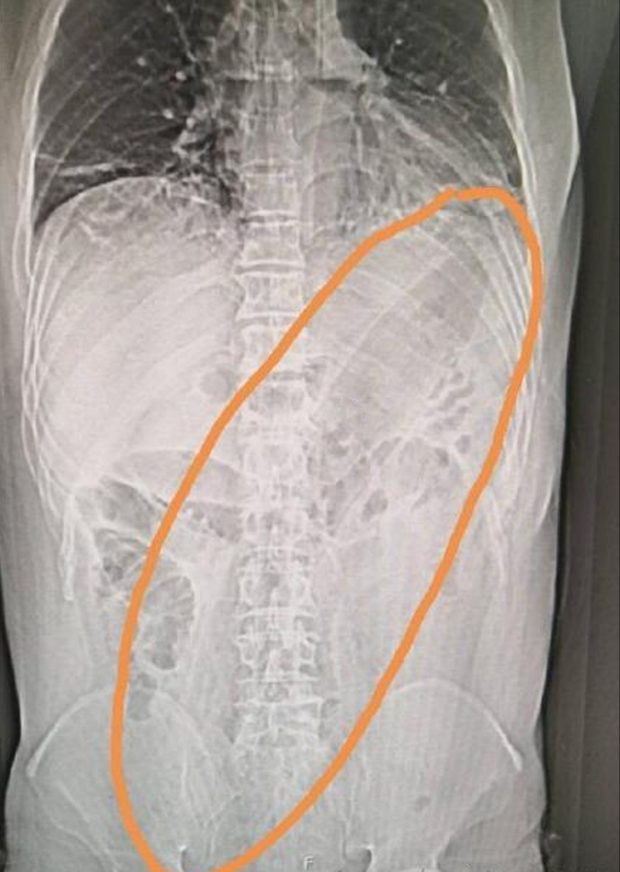

Các phim chụp Xquang cho thấy khi quả cà nằm ở ruột già làm cho phần ruột của ông này bị vỡ, bên cạnh đó, anh ta còn mắc chứng viêm phổi.

Phim chụp Xquang chỉ ra vị trí của quả cà trong cơ thể của người đàn ông (Ảnh: Metro)